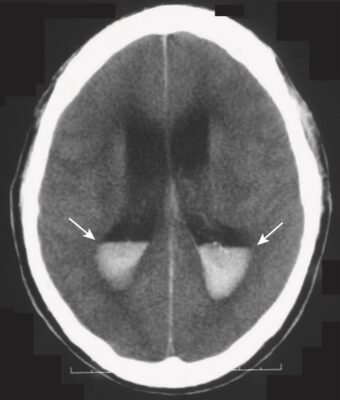

- Có thể có máu trong não thất (Hình 11).

- Hiệu ứng choán chỗ thường gặp. Hiệu ứng choán chỗ có thể ép các não thất và đẩy lệch não thất thứ 3 và vách ngăn sang bên đối diện. Sự dịch chuyển như vậy có thể gây ra tổn thương não hoặc mạch máu nghiêm trọng.